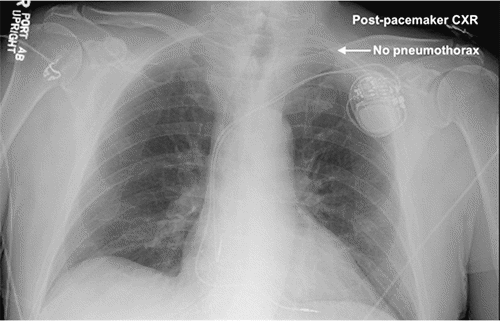

Figure 4. Repositioning of RV Pacemaker Lead. Published with Permission

Left chest tube is still in place, and there is no evidence of pneumothorax

The patient's dyspnea resolved, but he developed the same type of heart palpitations and dizziness that he had been experiencing before his pacemaker. His pacemaker was interrogated, and it was not possible to stimulate the ventricular lead, suggesting that the lead was free-floating in the ventricle. We concluded that the lead had been pulled out by the rapid reversal of his mediastinal shift after placing the chest tube. The patient was brought back to the operating room the next day to reposition the lead into the myocardium of the apical septum of the RV. His chest tube was water sealed and removed the following day. We had him use his CPAP overnight and confirmed no PTX 24 hours after chest tube removal. He was discharged home in stable condition and was doing well with no recurrent PTX at follow-up a week later.